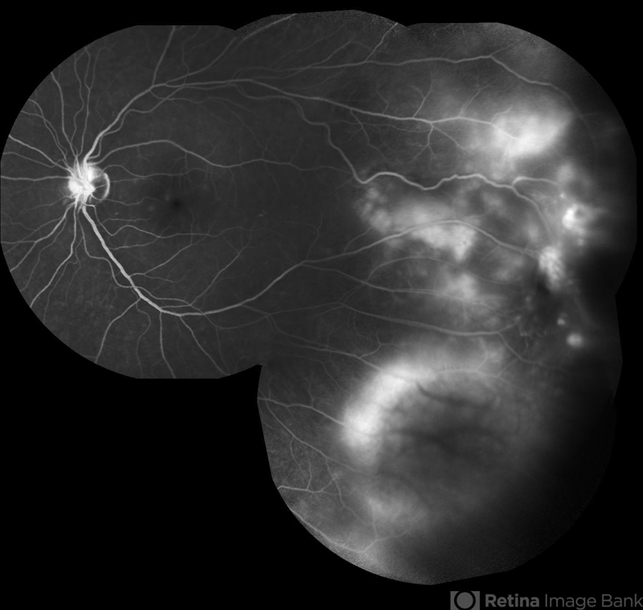

- Coats' disease, composite, fluorescein leakage, Heidelburg Spectralis, fluorescein angiogram (FA)

Scanning laser ophthalmoscope

Heidelberg Spectralis - Description

- Composite fluorescein angiogram of the left eye of a man with Coats Disease.